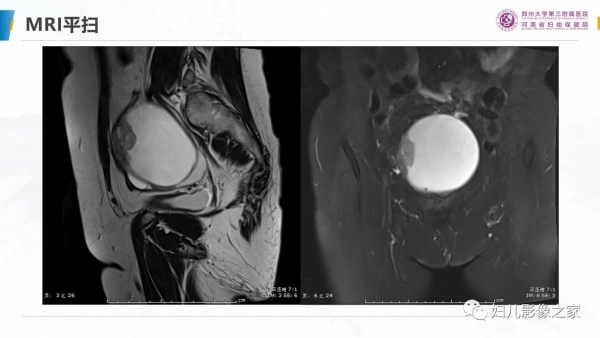

卵巢透明细胞癌

病史:患者女,57岁

主诉:尿频2月余,发现盆腔囊肿4天

现病史:2月前出现尿频尿急,4天前于当地医院彩超发现盆腔囊肿,无女性生殖器官出血,无腹痛

专科检查:于耻骨联合上方可触及拳头大小肿物